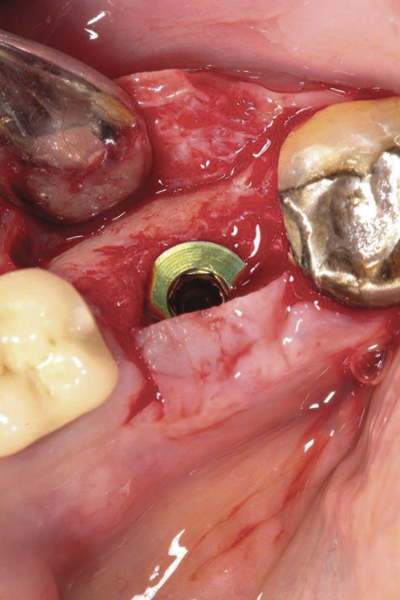

Fig 1. (Case 1) Tooth No. 19 manifested a buccal fistulous tract. Probing depth on the buccal was 8 mm.

Figure 1

Fig 11. An implant was placed in regenerated bone.

Figure 11